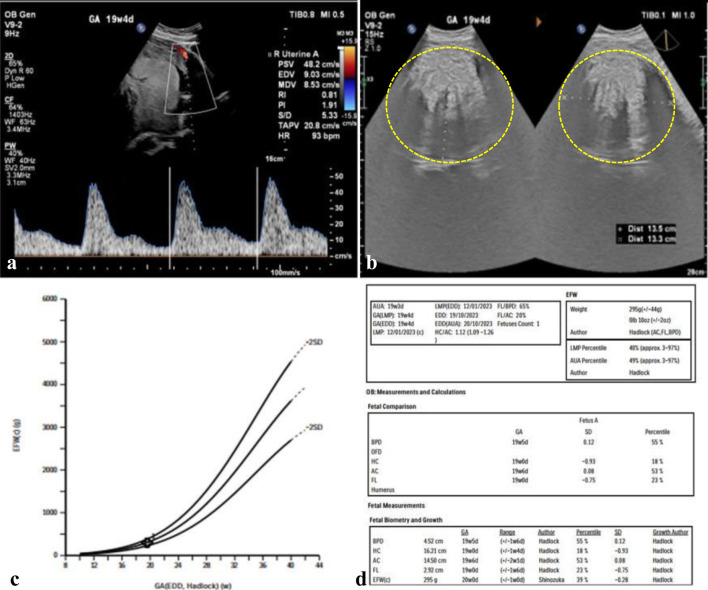

子宫肌瘤是一种良性肿瘤,影响了68.6%的女性,印度尼西亚的Hasan Sadikin医院报告的患病率在2.4%至12.46%之间。在怀孕期间,发病率降至0.1%至10.7%,但肌瘤仍可导致并发症。这个案例研究强调了一个复杂的妊娠与多个大子宫肌瘤的成功管理。孕36 ~ 37周的初迁症表现为子宫底1个大肌瘤(20 × 15 × 10 cm),前体6个小肌瘤。尽管面临这些挑战,但怀孕过程没有出现重大问题。进行了剖宫产手术,生下了一个体重2815克、身高46厘米的健康婴儿。该病例展示了对困难的产科情况的有效管理,强调了量身定制的护理和手术技巧在为母亲和婴儿实现有利结果方面的重要性。

Uterine fibroids, or myomas, are benign tumors affecting about 68.6% of women, with Indonesia's Hasan Sadikin Hospital reporting a prevalence between 2.4% and 12.46%. In pregnancy, the incidence drops to 0.1% to 10.7%, but fibroids can still lead to complications. This case study highlights the successful management of a complex pregnancy with multiple large uterine fibroids. A 36- to 37-week primigravida presented with a large intramural fibroid (20 × 15 × 10 cm) at the uterine fundus and six smaller fibroids in the anterior corpus. Despite these challenges, the pregnancy progressed without major issues. A cesarean section was performed, delivering a healthy baby weighing 2,815 g and measuring 46 cm. The case demonstrates effective management of a difficult obstetric situation, emphasizing the importance of tailored care and surgical skill in achieving favorable outcomes for both mother and baby.